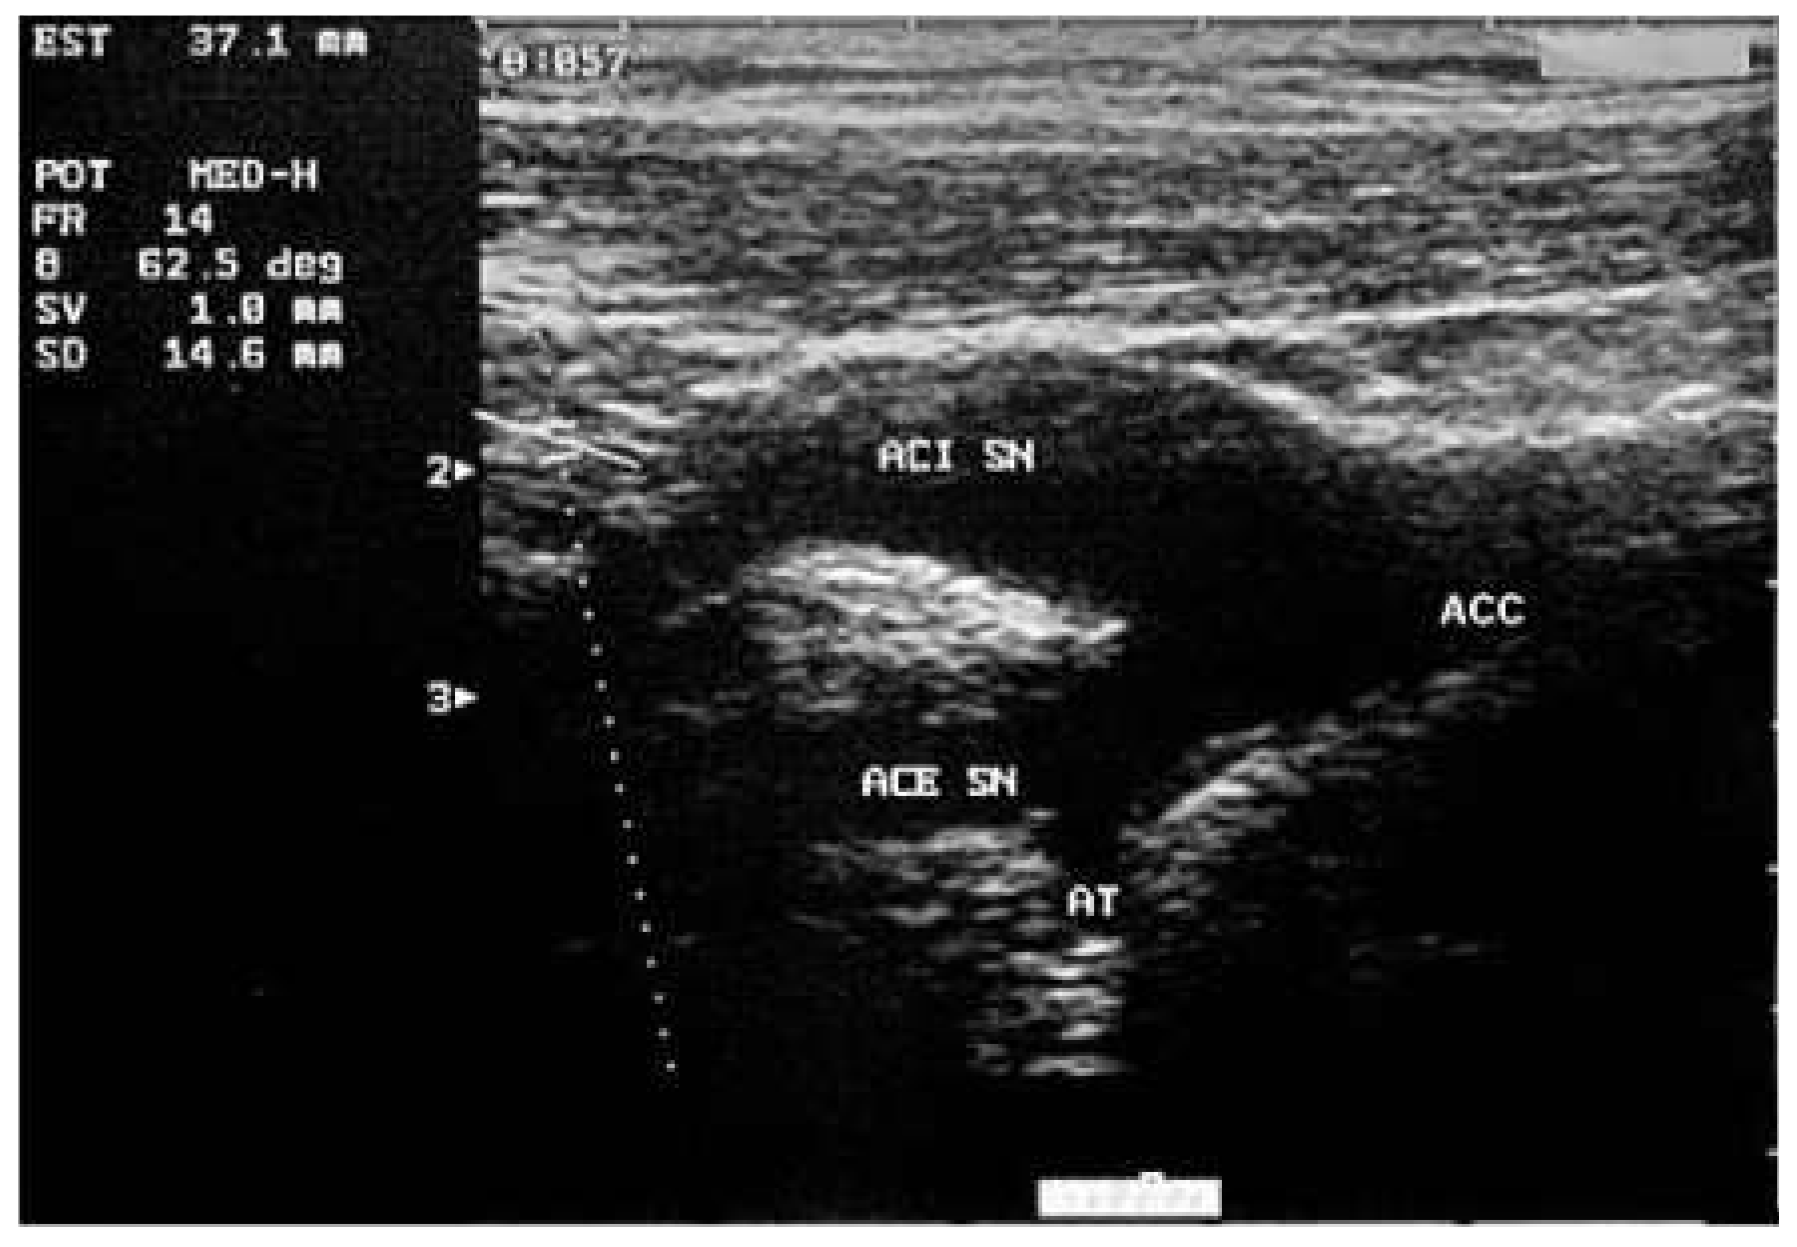

- Role of carotid plaque in cardiovascular risk prediction: comparison with CIMT